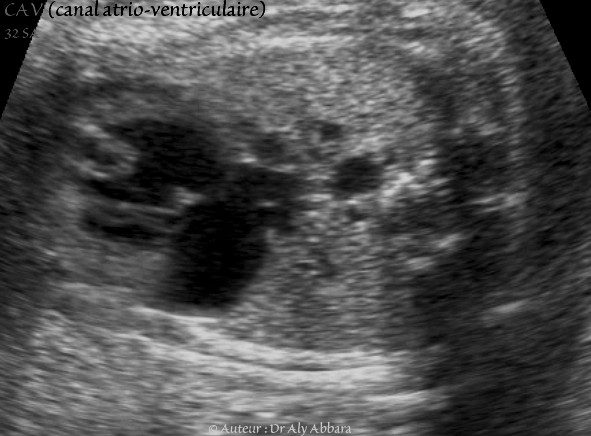

Canal atrio-ventriculaire complet - CAV - 32 SA - Vidéo et image animée échocardiographiques - القناة الأذينية البطينية

• Vidéo et image animée échographiques cardiaques montrant la présence de :

• un canal atrio-ventriculaire (CAV) complet.

• une valve atrio-ventriculaire (VAV) commune à une ouverture diastolique satisfaisante vers deux ventricules équilibrés (ventricule gauche "VG" et ventricule droit "VD" séparés pareillement par le septum interventriculaire "SIV" musculaire incomplet).

• une communication inter-auriculaire (CIA) de type ostium primum large aboutissant à la constitution d'une oreillette unique ou quasi unique (petit septum secundum "SS" au dôme de l'oreillette commune).

• la valve de Vieussens (V V) battant dans le secteur gauche de l'oreillette unique.

• une communication interventriculaire (CIV) très large ; il s'agit d'une communication de type de CIV d'admission.

• On observe également sur cette image la plaque modératrice (PM) battant dans le ventricule droit.

• L'aorte descendante (AO).

• Fœtus âgé de 32 SA trisomique 21.